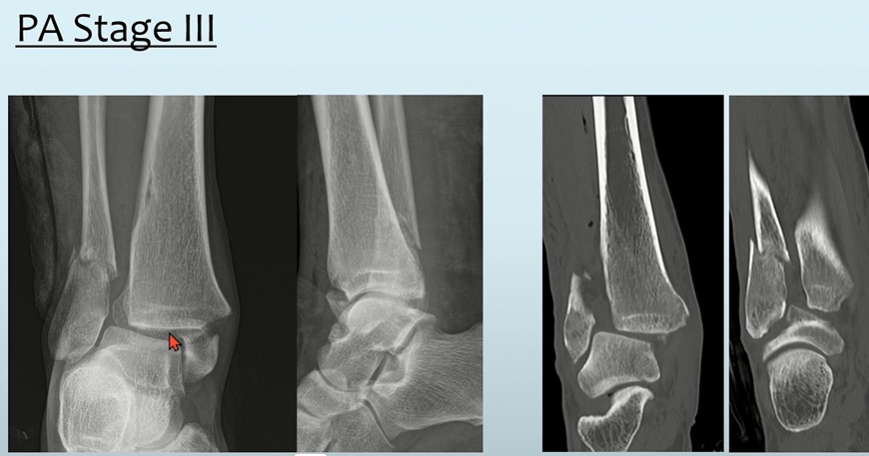

- Stage 1: MM 골절(Transverse 양상) 또는 Deltoid ligament injury

- Stage 2: PM 골절

- Stage 3: Distal fibula 골절 (외측은 높고, 내측은 낮은 양상) -> 그림을 통해서 이해!

실제 양상은 다음과 같습니다.